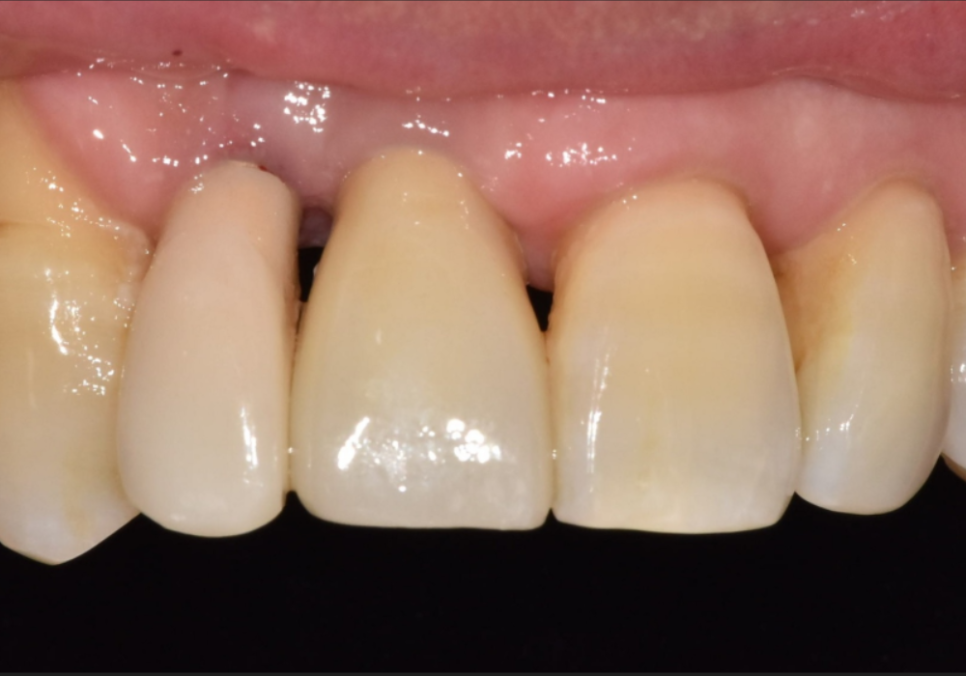

오른쪽 앞니(#12) 임플란트를 완성하고 난

며칠 뒤...

251022

환자분께서 중앙 앞니(#11)가

잇몸이 부었다가 가라앉기를 반복한다며

다시 내원하셨어요.

251125

자세히 살펴보니 고름이 빠져나온 흔적이 보이네요.

흔들림도 이전보다 심해진 상태였습니다.

C뿌리 끝 염증도 더 심해진 상황...

안타깝지만 이 치아도 발치 후

임플란트로 재건하기로 결정했습니다.